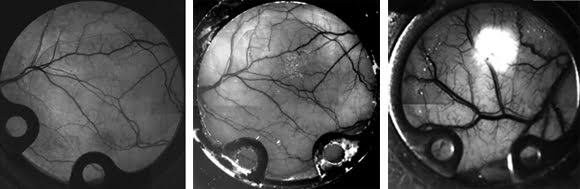

Body Vision: IR Applications and Lens Selection in Biomedical Settings

Although IR optics have long been used for military, surveillance and industrial applications, it is only recently that their full potential is being explored in biomedical settings. Common applications are to study veins in vivo, to image certain...

BioPhotonics, October 2010